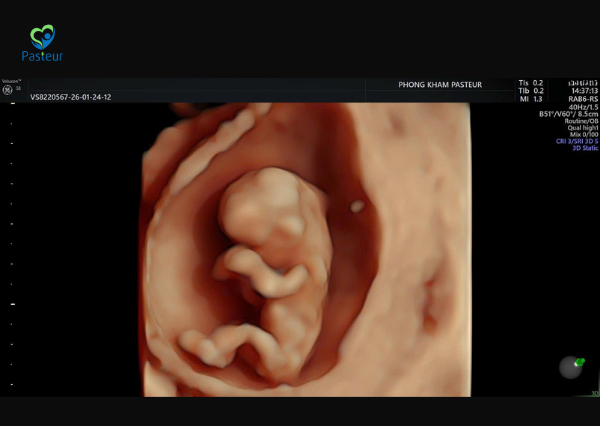

Siêu âm 12 tuần giúp kiểm tra độ mờ da gáy, xương mũi và sự phát triển của thai nhi để sàng lọc sớm dị tật bẩm sinh. Phòng khám đa khoa Pasteur chia sẻ các thông tin chi tiết về mốc siêu âm 12 tuần để các mẹ bầu cùng tìm hiểu.

Siêu âm ở tuần thai thứ 12 là một trong những mốc khám thai quan trọng trong tam cá nguyệt đầu tiên. Ở thời điểm này, thai nhi đã phát triển rõ ràng hơn về cấu trúc cơ thể, giúp bác sĩ có thể đánh giá nhiều chỉ số quan trọng liên quan đến sức khỏe và nguy cơ dị tật bẩm sinh.

Trong lần siêu âm ở tuần thai thứ 12, bác sĩ thường kiểm tra nhiều chỉ số quan trọng để đánh giá sự phát triển của thai nhi.

Siêu âm ở tuần thai thứ 12 là cột mốc quan trọng giúp đánh giá sự phát triển ban đầu của thai nhi và sàng lọc nguy cơ dị tật bẩm sinh. Thông qua lần siêu âm này, bác sĩ sẽ kiểm tra nhiều chỉ số quan trọng như độ mờ da gáy, xương mũi, chiều dài đầu – mông và nhịp tim thai.

Việc thực hiện siêu âm đúng thời điểm và kết hợp các xét nghiệm sàng lọc cần thiết sẽ giúp mẹ bầu theo dõi thai kỳ một cách an toàn và chủ động hơn. Mẹ bầu có thể tham khảo chi tiết video siêu âm thai 12 tuần được Ths Bs Đồng Thị Hồng Trang – Trưởng Đơn vị Sản phụ khoa Hiếm muộn chia sẻ tại đây.